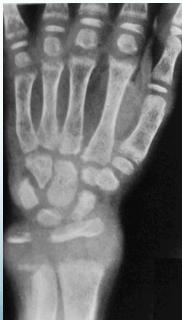

- Widened physis (epiphyseal growth plate)

- Cupping of metaphyseal end (weak new bone)

- Irregular metaphyseal end

- Osteopenia (decreased bone density)

- Thin cortex

- Enlarged ends of long bones:

- Wrists and knees most prominent

- Widened physis (first and most prominent finding)

- Metaphyseal changes:

- Cupping (due to weak new bone)

- Irregular margins